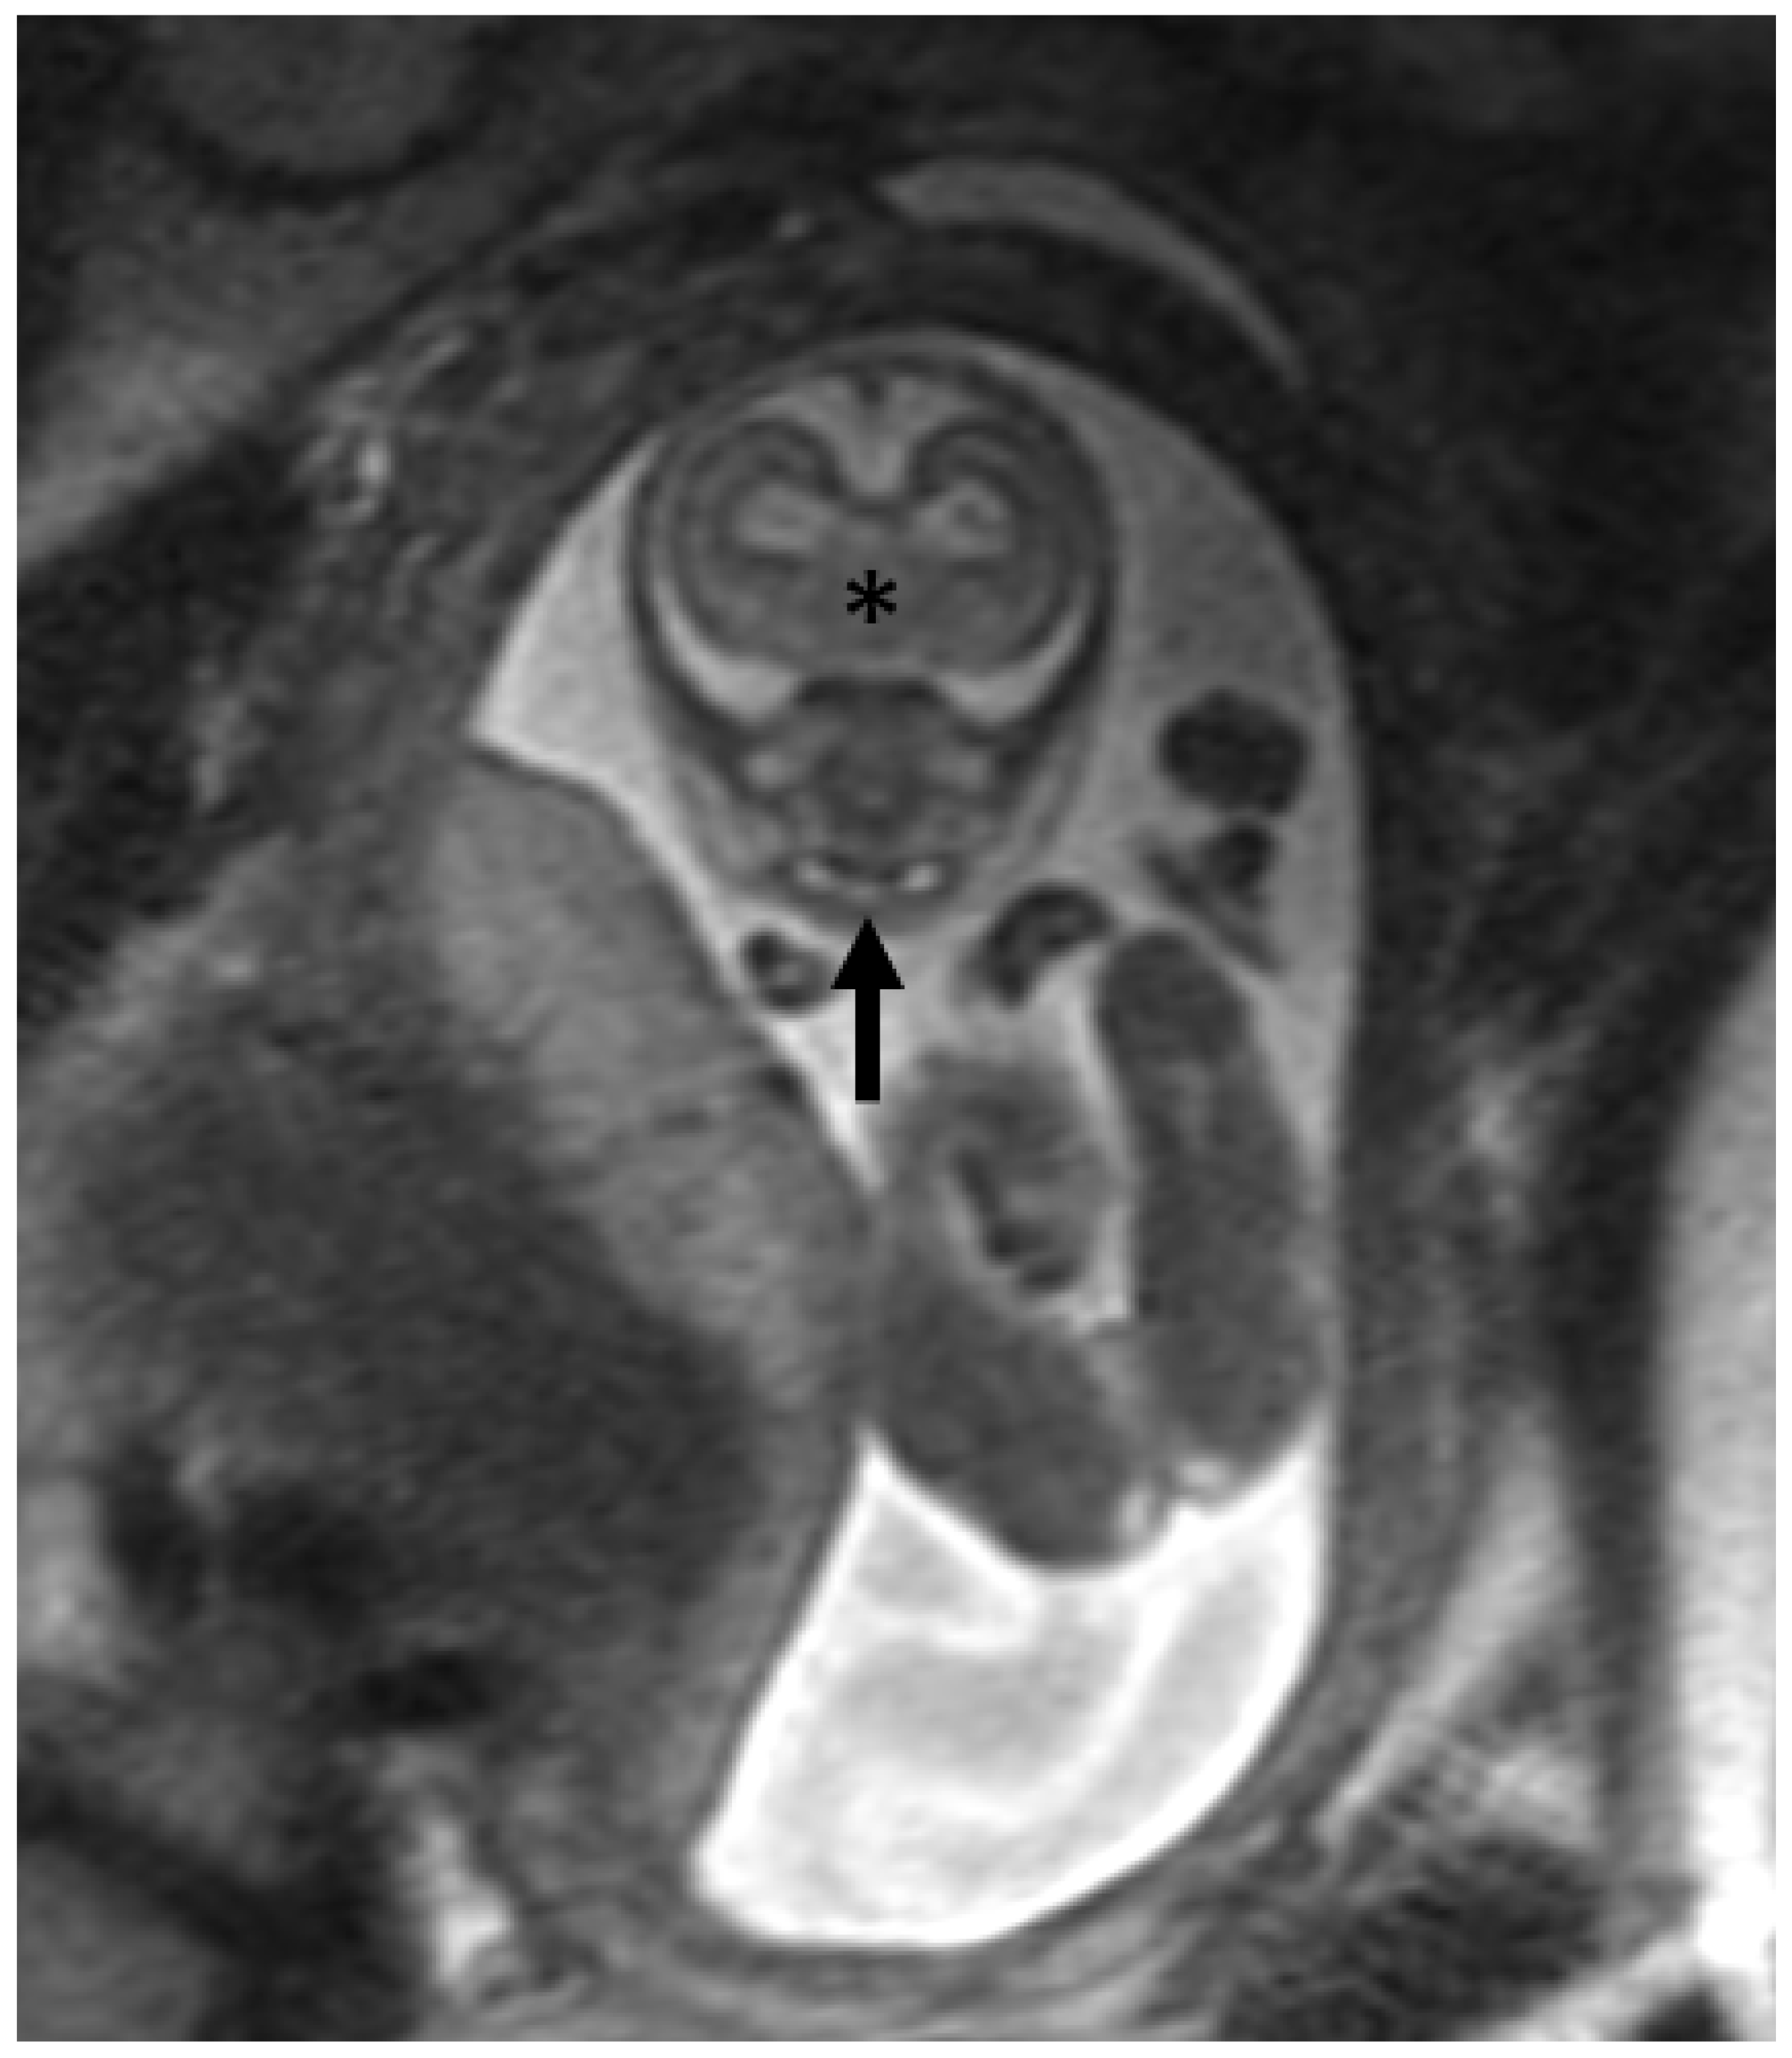

2. Materials and Methods

3. Results

3.2. Dental Development

3.3. Radiologic Correlations of Embryological Development